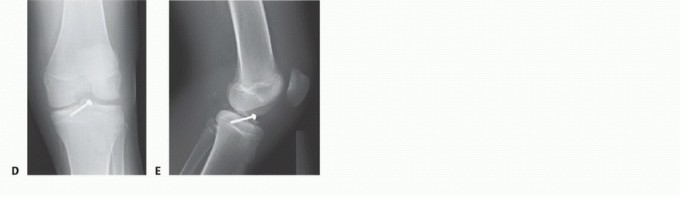

Once anatomic reduction of the fracture has been achieved, a 0.045-inch Kirschner wire is passed through the fracture fragment through the mid-parapatellar portal in the desired location of the final screw (TECH FIG 2A,B).

The position of the Kirschner wire is checked under fluoroscopy to ensure proper placement and to avoid traversing the growth plate.

Metal or resorbable screws can be used for fixation (TECH FIG 2C).

With metal screws, a 3.5- or 4.0-mm cannulated, selfdrilling self-tapping screw is used. The screw size is largely dependent on whether the fracture fragments will accommodate the screw.

With reduction maintained, the screw is gradually advanced under fluoroscopic guidance, making sure that the growth plate is not traversed.

AP and lateral radiographs of the knee are taken to document appropriate positioning of the screw and to document adequate reduction before closure (TECH FIG 2D,E).

TECH FIG 2 • Arthroscopic screw fixation. A. The fracture fragment is maintained using Kirschner wire(s).

* B. A cannulated metal screw is inserted under fluoroscopic guidance. C. A resorbable screw in position. As resorbable screw are not typically cannulated, placement requires removal of the Kirschner wire. A second Kirschner wire maintains reduction while the resorbable screw is inserted. D,E. AP and lateral radiographs, respectively, showing the tibial spine fracture fixed with a single cannulated screw with washer. Care should be taken to avoid crossing the physis with the screw.